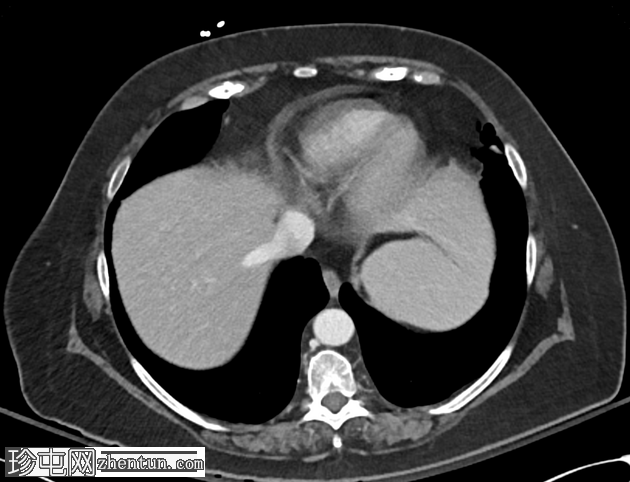

CT

轴位

1.png

平扫

多期CT扫描显示胆囊扩张,内含多发胆结石,胆囊壁增厚,胆囊周围脂肪组织炎症改变,提示急性胆囊炎。可见自发性高密度物质,与出血性内容物相符,符合出血性胆囊炎的影像学表现。

胆囊壁与十二指肠第二段相通,胆囊内可见气体,提示胆囊十二指肠瘘。

动脉期CT显示胆囊内侧缘有一结节状高密度病灶,平扫未见,静脉期CT显示该病灶,符合胆囊假性动脉瘤的影像学表现。